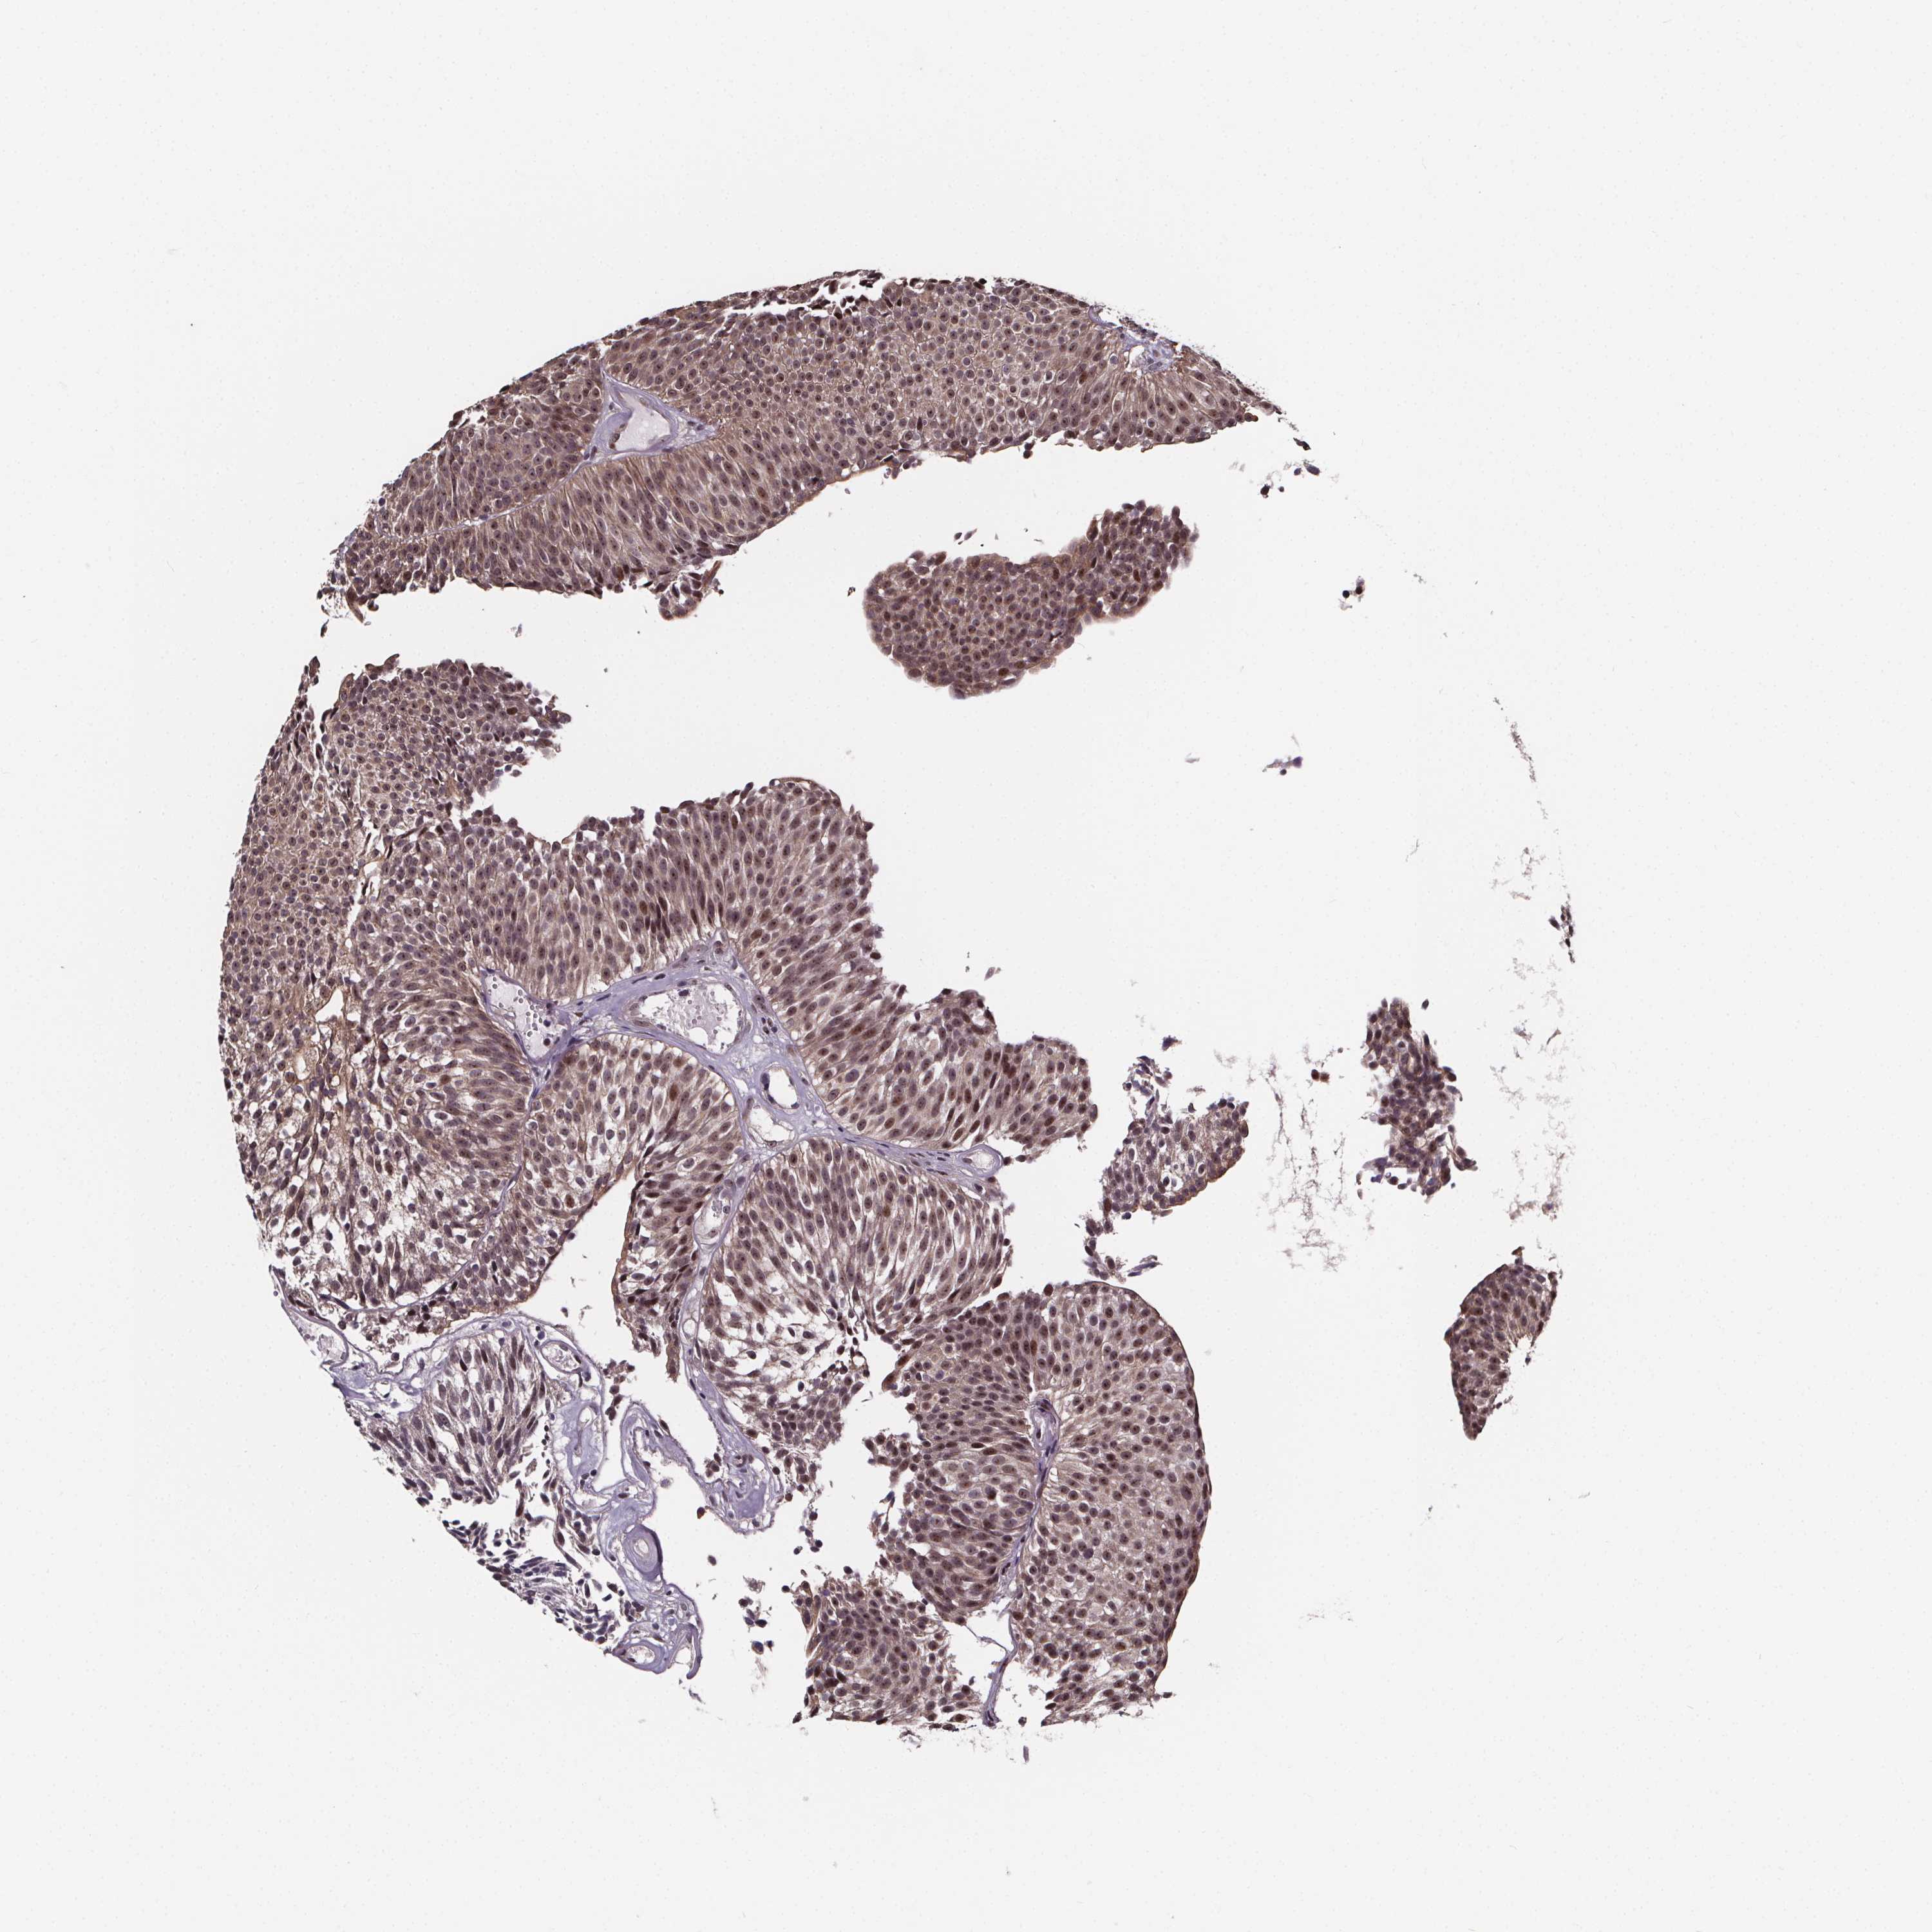

UROTHELIAL CANCER - Protein expressioni

A mouse-over function shows sample information and annotation data. Click on an image to view it in a full screen mode. Samples can be filtered based on level of antibody staining by selecting one or several of the following categories: high, medium, low and not detected. The assay and annotation is described here.

Note that samples used for immunohistochemistry by the Human Protein Atlas do not correspond to samples in the TCGA dataset.

Antibody stainingi

Antibody staining in the annotated cell types in the current human tissue is reported as not detected, low, medium, or high, based on conventional immunohistochemistry profiling in selected tissues. This score is based on the combination of the staining intensity and fraction of stained cells.

Each image is clickable and will lead to virtual microscopy that enables deeper exploration of all samples and also displays staining intensity scores, fraction scores and subcellular localization as well as patient and tissue information for each sample.

Antibody HPA068416

Staining

High

Medium

Low

Not detected

Intensity

Strong

Moderate

Weak

Negative

Quantity

>75%

75%-25%

<25%

None

Location

Nuclear

Cytoplasmic/membranous

Cytoplasmic/membranous,nuclear

Urothelial carcinoma, High grade

Urothelial carcinoma, NOS

Urothelial carcinoma, Low grade